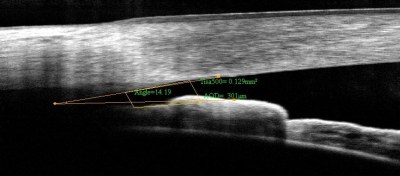

6) Λεπτός κερατοειδής

Ο κερατοειδής είναι ο διαφανής χιτώνας του ματιού μας που ευρίσκεται εμπρός από την ίριδα. Κερατοειδής λεπτότερος του μέσου όρου αποτελεί παράγοντα κινδύνου τόσο για την εμφάνιση όσο και για την εξέλιξη του γλαυκώματος.